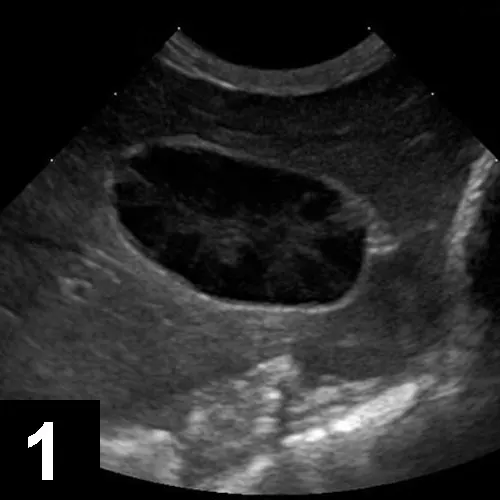

Featured Image

Figure 1B

In this ultrasound, the gallbladder contents show a narrow hypoechoic region at the periphery with central heterogeneous material filling most of the gallbladder lumen. The irregular hypoechoic areas within the heterogeneous material correspond to areas within the bile accretion with a higher mucus content admixed with areas of echogenic bile. The gallbladder contents were immobile when the patient was repositioned.